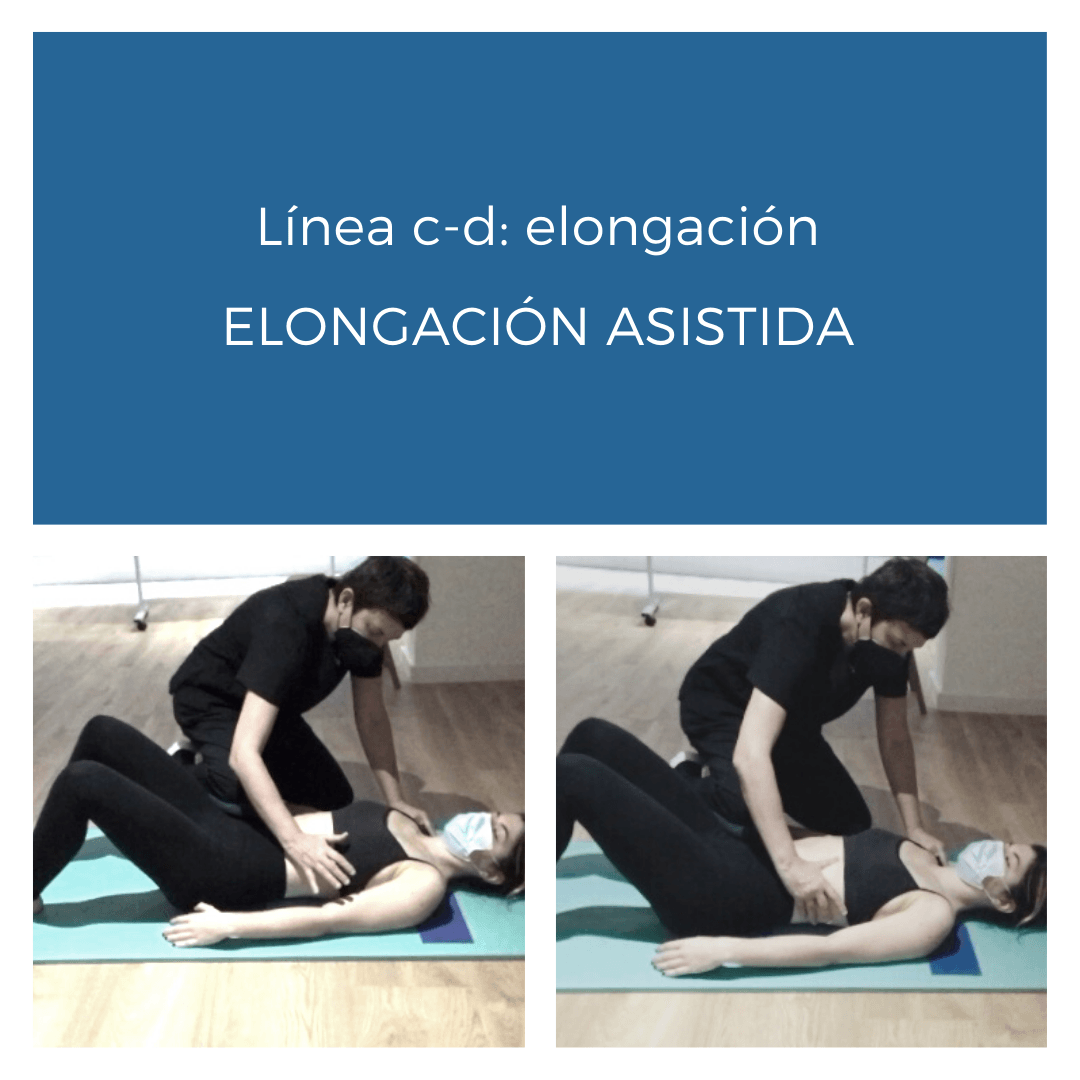

-Elongar el segmento c-d

EJERCICIO DE AUTOELONGACIÓN DE LA LÍNEA c-d